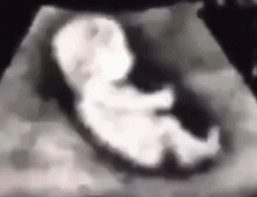

医生及时加强了保胎措施:升级了抗凝药物(依诺肝素钠)并加用了绒促性素。后续超声监测显示宝宝发育良好!

在整个孕期坚持定期检查,她成功足月剖宫产下一名健康的小宝贝。